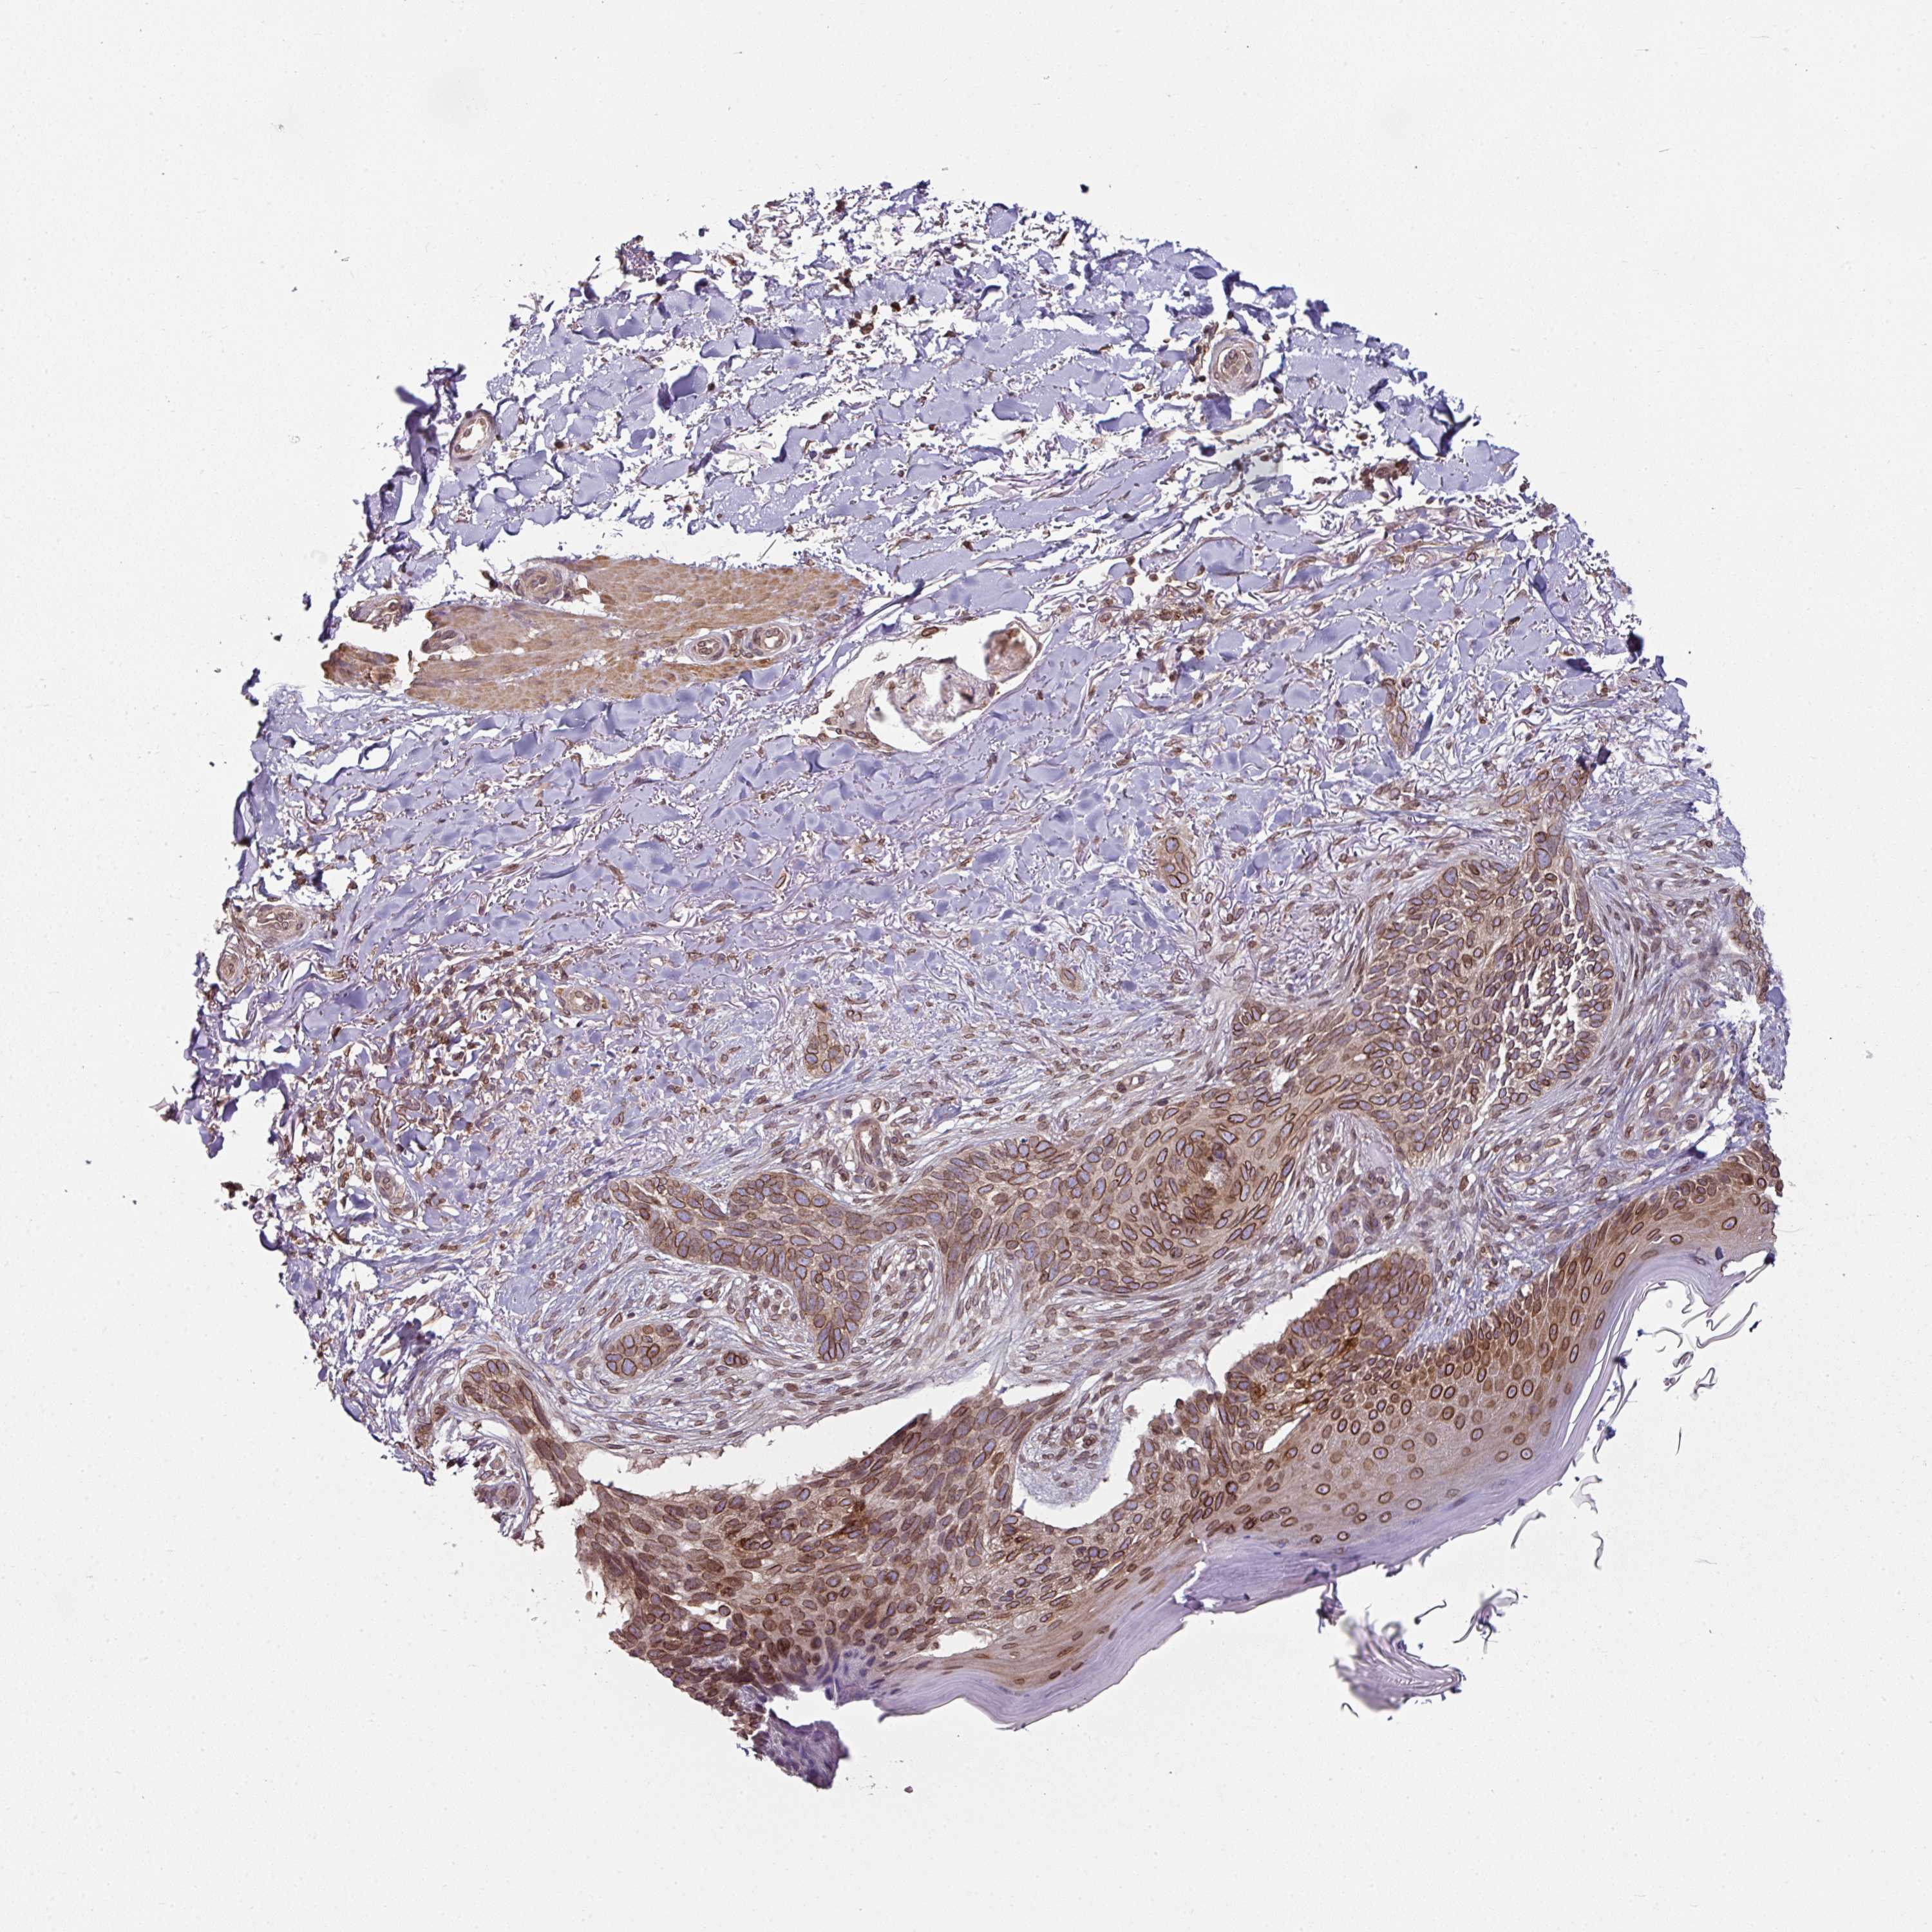

Basal cell and squamous cell cancer

SKIN CANCER - Protein expressioni

A mouse-over function shows sample information and annotation data. Click on an image to view it in a full screen mode. Samples can be filtered based on level of antibody staining by selecting one or several of the following categories: high, medium, low and not detected. The assay and annotation is described here.

Antibody stainingi

Antibody staining in the annotated cell types in the current human tissue is reported as not detected, low, medium, or high, based on conventional immunohistochemistry profiling in selected tissues. This score is based on the combination of the staining intensity and fraction of stained cells.

Each image is clickable and will lead to virtual microscopy that enables deeper exploration of all samples and also displays staining intensity scores, fraction scores and subcellular localization as well as patient and tissue information for each sample.

Antibody HPA050110

Antibody CAB004293

Squamous cell carcinoma, NOS